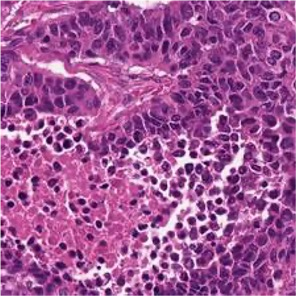

Multiple instance learning (MIL) is a powerful approach to classify whole slide images (WSIs) for diagnostic pathology. A fundamental challenge of MIL on WSI classification is to discover the \textit{critical instances} that trigger the bag label. However, previous methods are primarily designed under the independent and identical distribution hypothesis (\textit{i.i.d}), ignoring either the correlations between instances or heterogeneity of tumours. In this paper, we propose a novel multiplex-detection-based multiple instance learning (MDMIL) to tackle the issues above. Specifically, MDMIL is constructed by the internal query generation module (IQGM) and the multiplex detection module (MDM) and assisted by the memory-based contrastive loss during training. Firstly, IQGM gives the probability of instances and generates the internal query (IQ) for the subsequent MDM by aggregating highly reliable features after the distribution analysis. Secondly, the multiplex-detection cross-attention (MDCA) and multi-head self-attention (MHSA) in MDM cooperate to generate the final representations for the WSI. In this process, the IQ and trainable variational query (VQ) successfully build up the connections between instances and significantly improve the model's robustness toward heterogeneous tumours. At last, to further enforce constraints in the feature space and stabilize the training process, we adopt a memory-based contrastive loss, which is practicable for WSI classification even with a single sample as input in each iteration. We conduct experiments on three computational pathology datasets, e.g., CAMELYON16, TCGA-NSCLC, and TCGA-RCC datasets. The superior accuracy and AUC demonstrate the superiority of our proposed MDMIL over other state-of-the-art methods.